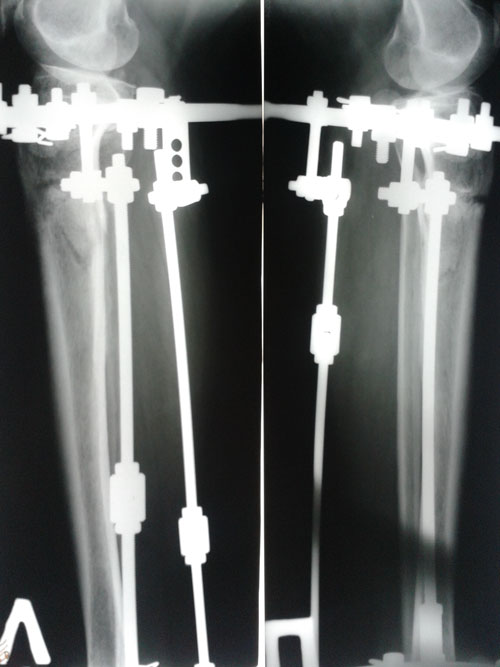

Ножки на сегодня.

Пациентка делает упор на правую ногу, левую щадит.